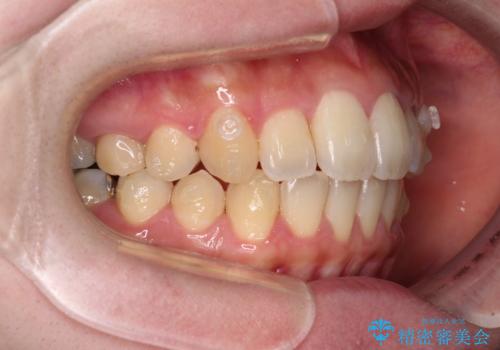

- 捻れた前歯が飛び出しており、口が閉じにくいとのことで来院された患者様です。

出っ歯というわけではないものの、前歯の捻転により口唇が押し出されている状態でした。

親知らずを抜去し、歯列全体を後方に移動させつつ、IPR(歯と歯の間を削る)でスペースを獲得し、インビザラインを用いて叢生を解消しながら前歯の突出を改善することとしました。